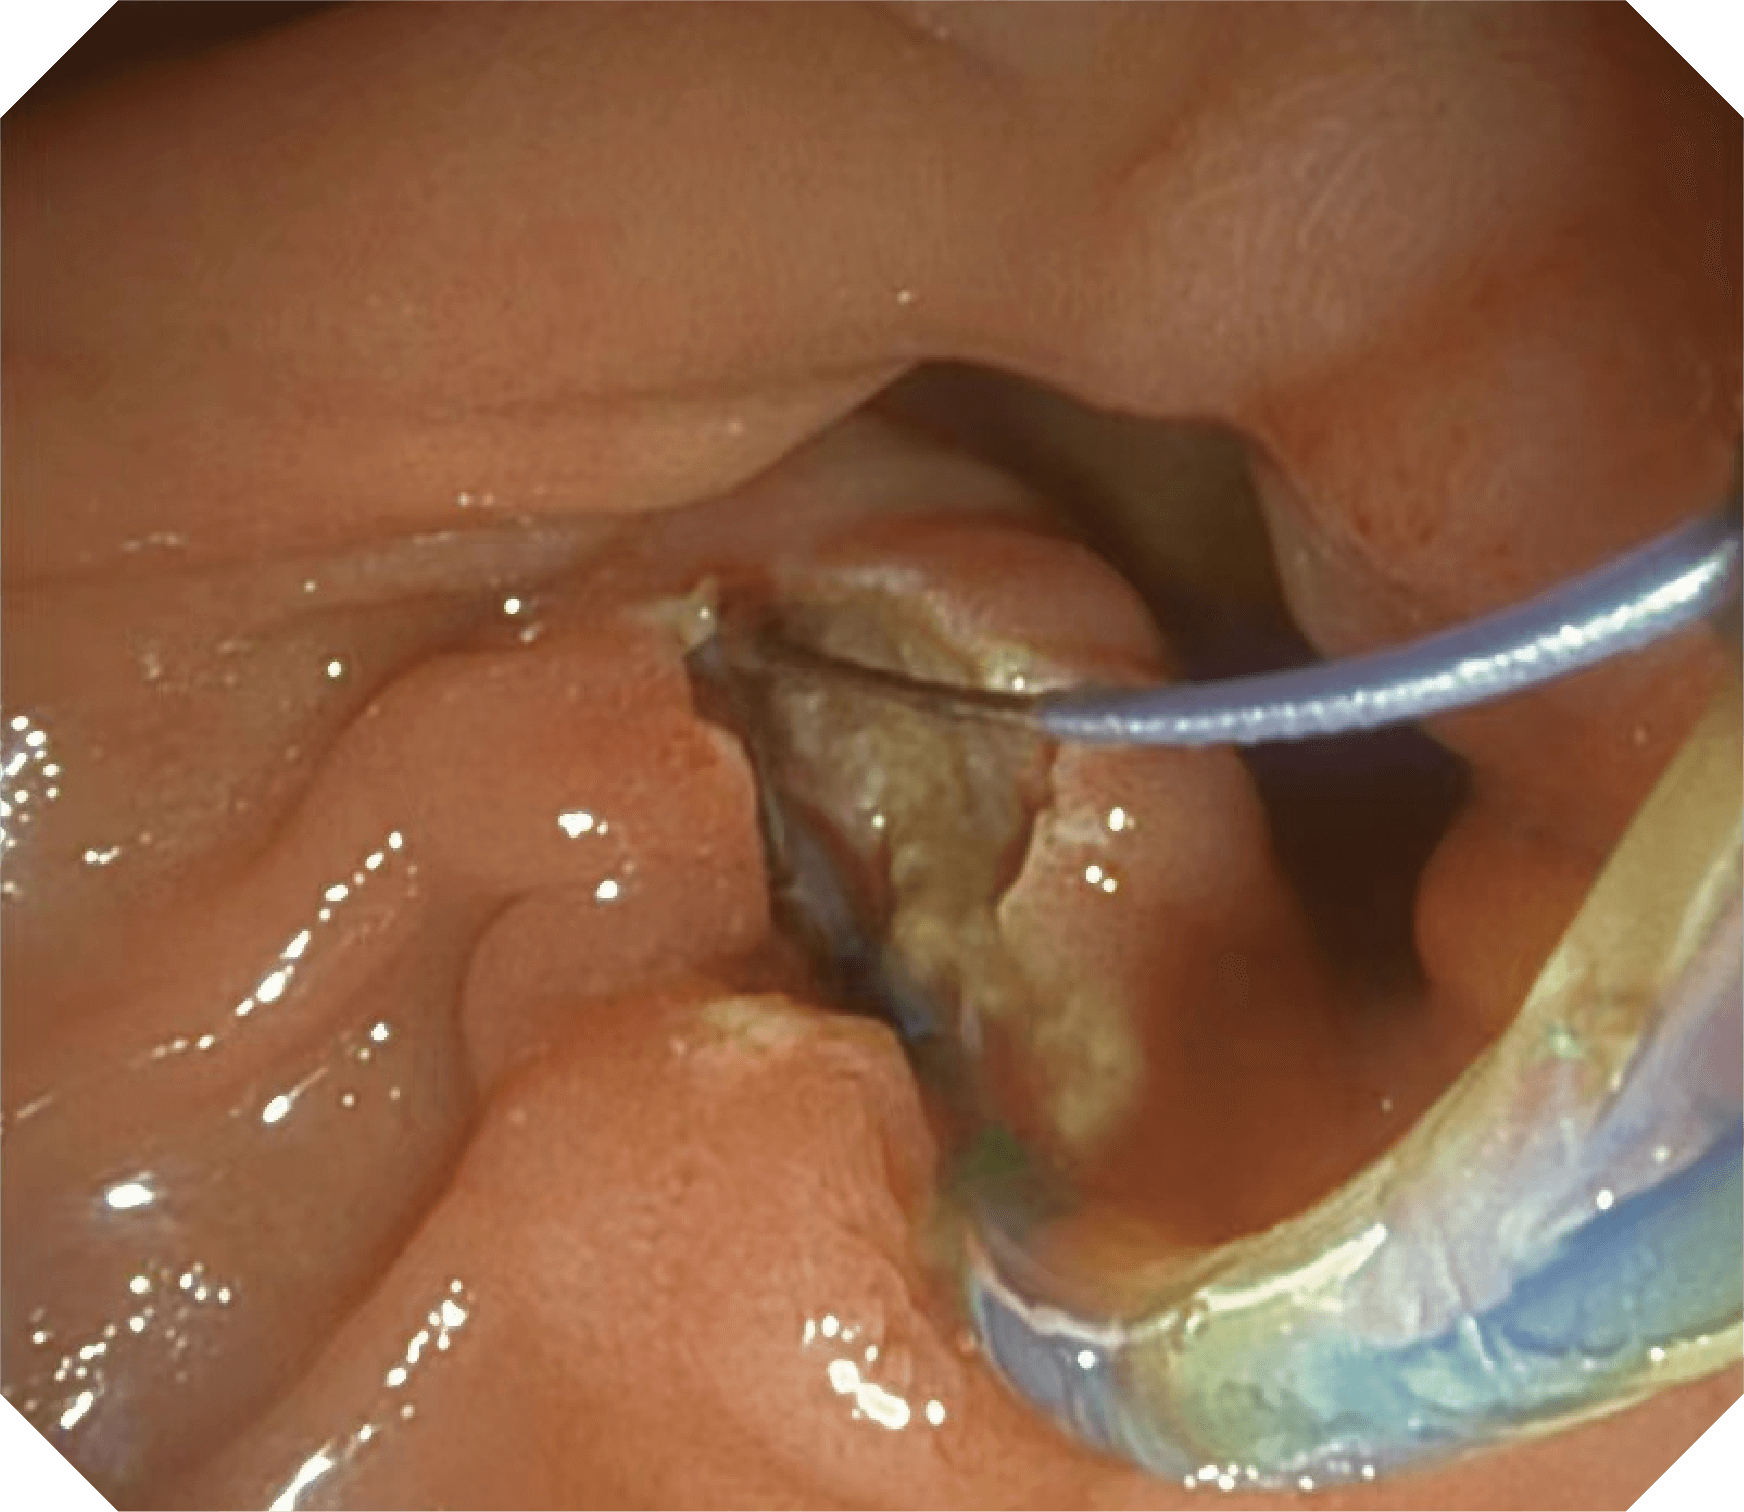

优异的手术器械抬举性

更好的通过性,更稳定的镜体支撑力

当切开刀伸出视野外时,导向面引导其回归视野